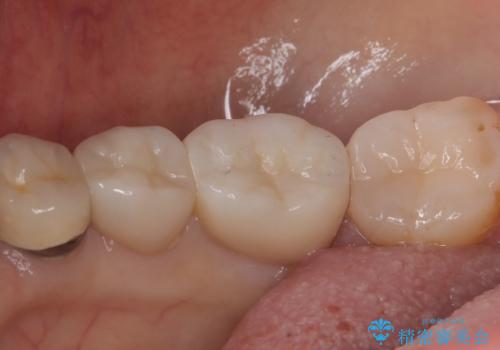

- 主訴:下の歯に詰まっている銀が笑うと見えて嫌だから白くしたい

右下7番目の歯に保険適用のメタルインレーが入っており、大きなう蝕などは認めなかったため概形は大きく変えずセラミックインレーへやり替えとなりました。

やり替える過程で古い裏層材やカリエスは全て除去し、新たにCR裏層を行っています。

セラミックインレーセット時はラバーダム防湿を行っています。